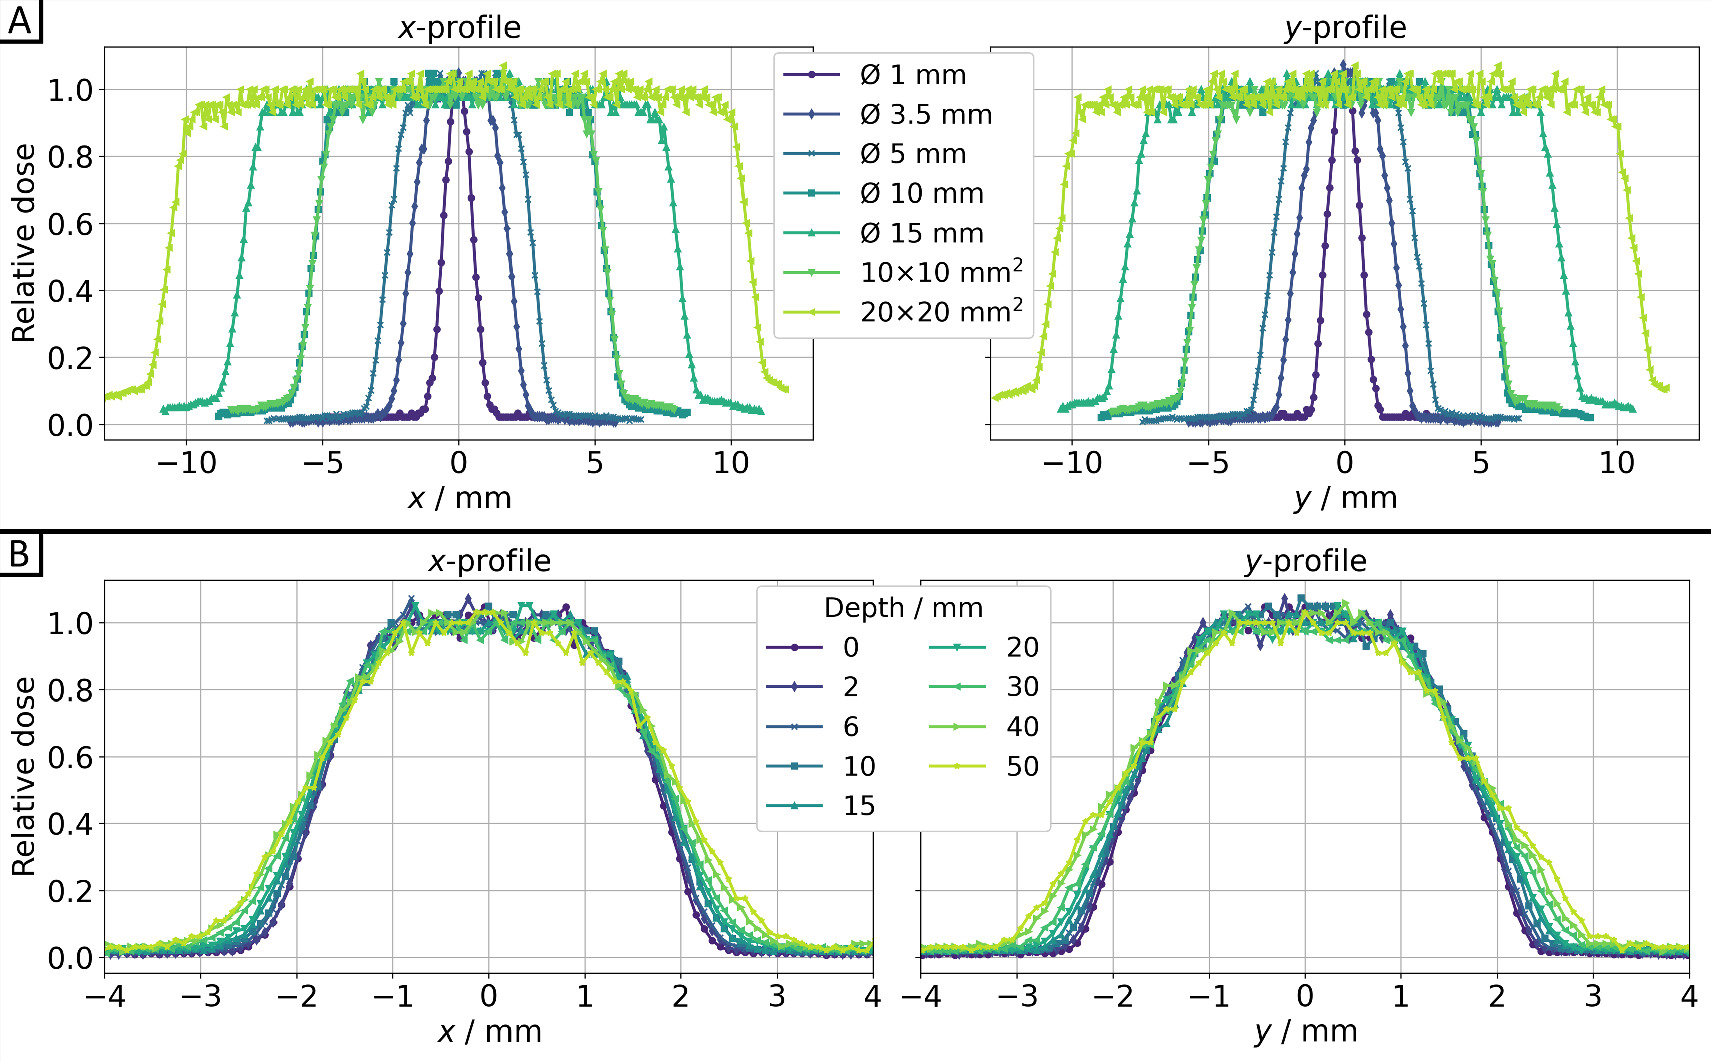

3.2. Photon beam characterization

In figure 5, both cross-plane (x-profile) and in-plane (y-profile) profiles are shown for seven different collimators in 10 mm (water) depth (figures 5(A)) and at various depths along the beam path for the Ø3.5 mm collimator (figure 5(B)). The dose values were consistently averaged (median) over five EBT3 films for each time and depth of the solid water slab phantom from figure 3(C). The corresponding full width at half maximum (FWHM) and penumbra values can be found in table 1. Gaussian fitting was applied for the Ø1 mm collimator (R2 = 0.992), while sigmoid edge fitting was used for the remaining collimators (R2 > 0.990). This involved utilizing 50% of the central beam dose for FWHM and 20%/80% of the central beam dose for the penumbra calculations. All collimators exhibit expected FWHMs and a slight increase in penumbra with larger collimators. For the Ø3.5 mm collimator, both the FWHM and penumbra increase linearly with depth for both profiles, as anticipated.

Figure 5. Dose profiles for the cross-plane direction (x-profile) and in-plane direction (y-profile) for 200 kV x-rays (0.5 mm Cu filter, HVL: 1.03 mm Cu) of SmART+ IB (A) for all collimators at depth z = 10 mm, as well as (B) for the Ø3.5 mm collimator for different depths, all measured using EBT3 films (relative measurement uncertainties <7%).

The dose rates for all investigated collimators can be found in table 1. The dose rate was calculated from the difference between the 80 s and 20 s exposed films, each including all dose values from a 9 × 9 px2 (0.76 × 0.76 mm2) field centered around the center of mass. It is evident that for larger collimators, the available dose rate is higher. Based on the dose rate values, relative depth dose profiles were determined and illustrated in figure 6, with normalization to a depth of 10 mm due to the greater fluctuation of surface dose values.

Figure 6. Relative depth dose for photon irradiation for all collimators at 200 kV x-rays (0.5 mm Cu filter, HVL: 1.03 mm Cu) of SmART+ IB, measured with EBT3 films (relative measurement uncertainties <7%). Normalization to a depth z = 10 mm was performed due to the greater fluctuation of surface dose values.